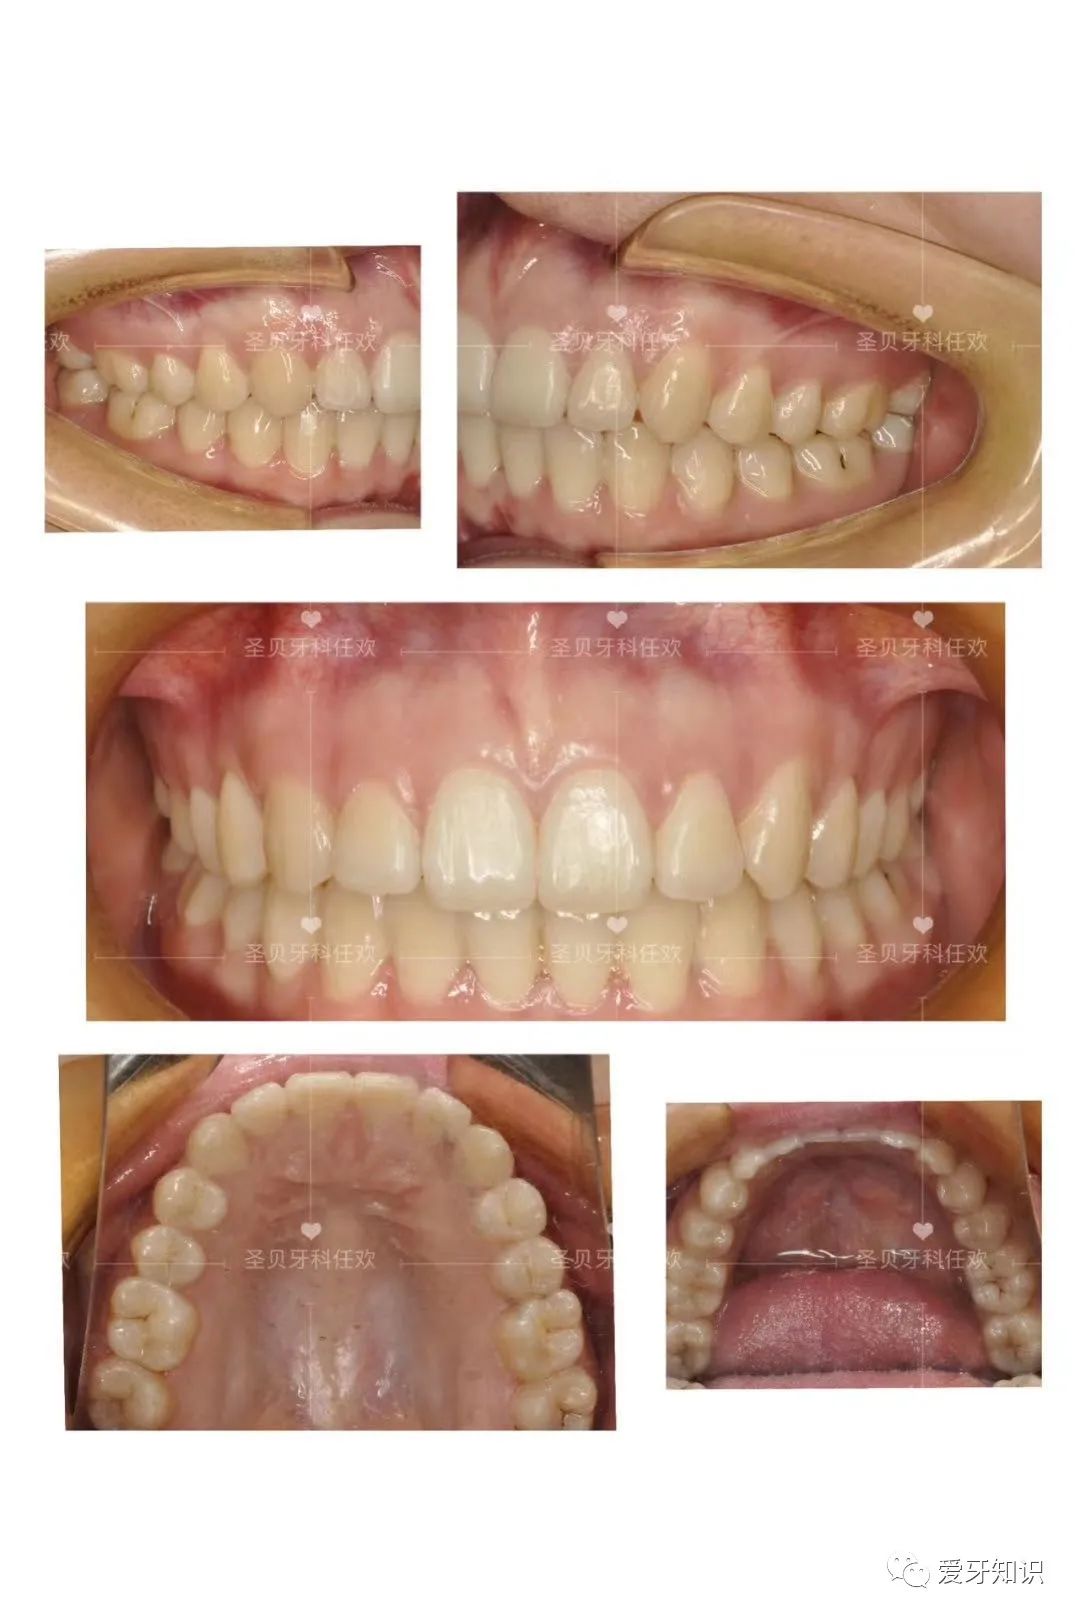

@这位同学 25岁 问题:牙齿不齐,咬合不好,技术:正雅隐形牙套矫正“好看又美观,价格才15800元!”

矫正前后对比以前的牙齿那叫一个惨不忍睹,拍照不敢笑,跟人说话也下意识的挡着嘴。以前同学们总是背地里叫我“牙擦苏”。

现在每天都很爱笑庆幸自己悬着了牙齿矫正,比我想象中便宜很多,口腔CT检查、拍片、专家制定矫正方案都给免了,碰上活动秒杀价,真是太划算了!一口整齐大白牙正式上线,颜值和气质直线提升,笑起来太美啦~